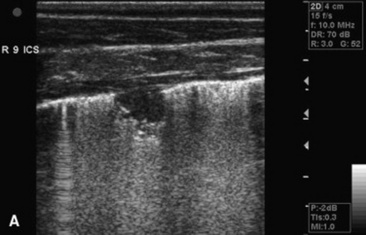

Ultrasonography

Thoracic ultrasonography, a companion to thoracic radiography, is useful for diagnostic, therapeutic, and prognostic evaluation of the extraparenchymal thorax, the pleural space, and the peripheral (superficial) parenchyma of the lung. Unlike thoracic radiography, in which specialized equipment is needed to image the adult large animal, thoracic ultrasonography is an imaging technique readily available to most practitioners. In many instances it is superior to thoracic radiography as an imaging method; examples include evaluation of pleural effusions, assessment of thoracic trauma, evaluation of neoplasms or granulomata, detection of mediastinal masses or abscesses, and guidance of transthoracic lung biopsy.9,10 Ultrasonography is considered greatly superior to thoracic radiography in the detection of rib fractures.11 This imaging technique should be considered for complete evaluation of any large animal with suspected or diagnosed pulmonary disease.

Ultrasonography is generally performed with the patient standing, although in neonates lateral recumbency may be preferred or even necessary, and sound waves are generated by piezoelectric crystals and transmitted to the area of interest through a skin coupling gel, with subsequently reflected echoes detected by the same crystal. Echo signals from all tissue interfaces are displayed on a screen; the image can be photographed for a permanent record or stored digitally. Air trapped beneath the haired skin can interfere with the process, as can excessive skin dirt, so preparation of the acoustic window usually involves hair removal and cleansing in order to get the best image possible.

Although ultrasound waves will not penetrate the aerated portion of the lung, limiting the examination to extraparenchymal surfaces in normal horses, ultrasonography is superior to thoracic radiography in evaluation of these areas of the chest. Small amounts of pleural fluid that would be missed on auscultation, percussion, or thoracic radiographs can be detected, and the amount and character of pleural effusion in each hemithorax can be separately evaluated.9 Clear fluid is anechoic, but inflammatory cells, gas, and fibrin are echogenic, causing opacities that can be seen floating in pleural fluid and altering the general echogenicity of the fluid. Because of this, ultrasound is the method of choice for diagnosis and monitoring of pleural space disease. Ultrasonography should be used to guide catheter placement for drainage of accumulated fluid in the pleural space. The pleural surfaces are imaged well by ultrasound, with thickened or roughened areas easily detected. Lack of normal independent movement of the visceral and parietal pleural surfaces during the respiratory cycle, suggestive of adhesion formation, can be readily monitored.9,10

Consolidated lung is a better acoustic medium than aerated parenchyma and can be well visualized. If there is pleuropneumonia with consolidation or atelectasis caused by compression of the ventral lung by pleural effusion, it will be evident. Pulmonary abscesses or masses extending to the lung surface can be imaged, and ultrasound can be used for guidance for transthoracic biopsy.9,10 Thoracic radiography remains superior to ultrasound in diagnosis of pulmonary parenchymal disease and pneumothorax, but combined the two techniques will improve patient management diagnostically and therapeutically.